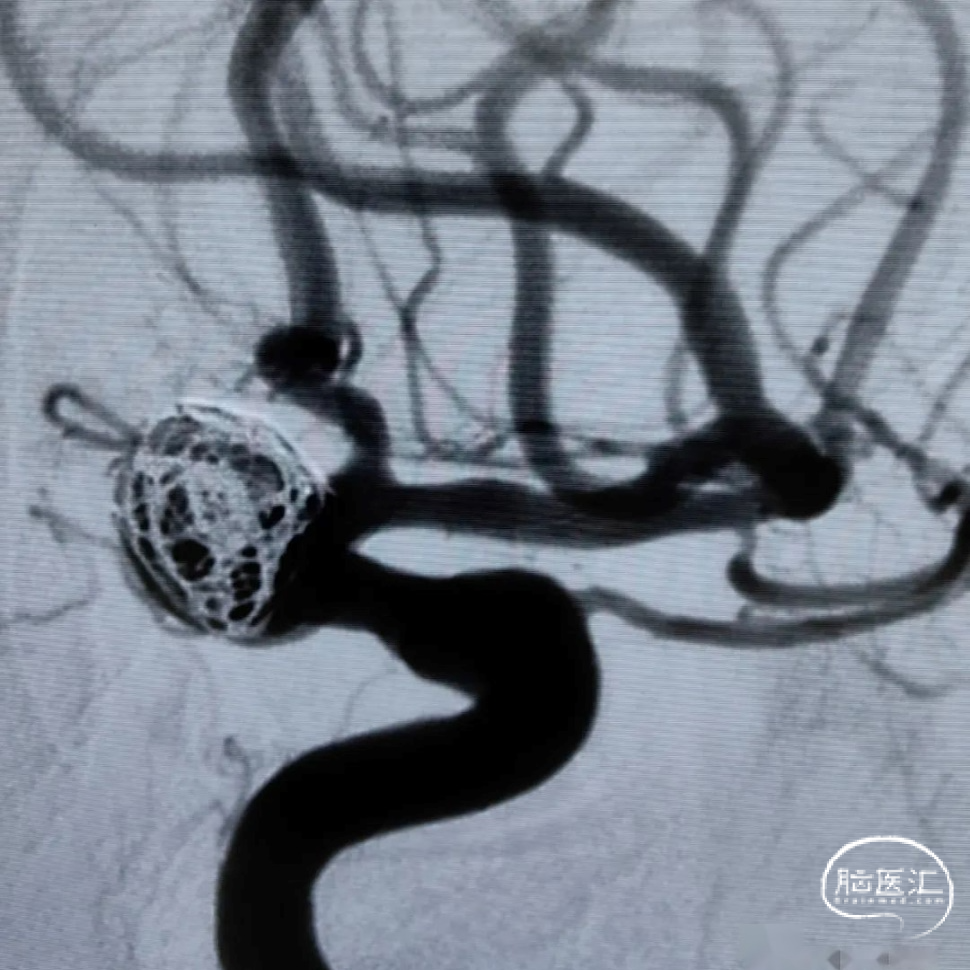

微导丝支架尾端按摩,使支架充分贴壁。

术后即刻影像,造影示动脉瘤腔内空虚处滞留明显,载瘤动脉通畅。遂撤出弹簧圈微导管,支架输送系统。